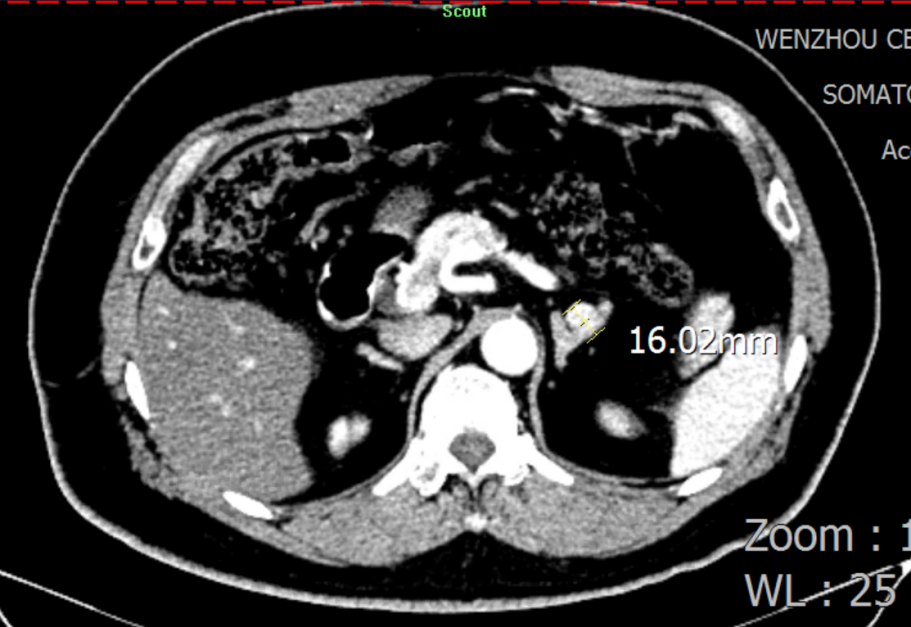

二十年前被诊断为高血压 血压控制不睬想引发两次脑出血 高峻爷的病史要从二十年前提及。2003年,在一次体检中被发明血压升高抵达150/100mmHg,经外地医院诊断为高血压,时值壮年的高先生没有太在意。 然而,让人没想到的是,2011年,在完成一次高负荷的事情后,高先生马上感应天旋地转,再度醒来时已经接受了小脑血肿扫除和去骨瓣减压术。 “幸亏救护车来得实时,我的命是脑外科医生从死神手里夺回来的。”之后,高先生提前过上了退休生涯,只管遵医嘱准时服用降压药,但血压控制并不睬想,还被诊断为重度壅闭性睡眠呼吸障碍综合征,使得血压控制更难了。 2019年,149/85mmHg的血压再次向他的血管提倡攻击,高先生因右侧小脑血肿再次入院。这对刚刚脱离手杖的高先生而言,又是一次重大攻击。 二十年后经精准诊断 行左侧肾上腺切除术后病情显著改善 心肌标记物、肝肾功效、血糖、血脂、甲状腺功效、BNP/NT-proBNP、超敏肌钙卵白、电解质……厚厚的一沓检测报告中,晚年科陈主任关注到有十几张血钾、尿钾异常报告。通过询问家族病史,陈主任相识到高峻爷的母亲和弟弟均患有高血压、低钾血症,且恒久服用氯化钾缓释片,其母亲已于十年前因脑出血去世。 陈主任决议将高峻爷以高血压伴低钾血症病因收治入院,并复查血钾,行盐皮质激素相关高血压筛查及全腹部CT扫描。 盐皮质激素相关高血压筛查(卧位 早上6点) 盐皮质激素相关高血压筛查(立位 早上8点) 检测报告出来后,陈主任第一时间请内渗透科余主任会诊。余主任看了报告,第一时间想到了最常见的引起高血压伴低钾血症的内渗透科疾病——原发性醛固酮增多症(简称“原醛症”)。 “以前,各人都以为原醛症是一个少见病,遇到高血压伴低血钾就直接给患者上螺内酯。着实原醛症有六种分型,每种都有差别的诊疗计划。若是是醛固酮瘤,高血压甚至有治愈的希望。”余主任感应很遗憾,“这个检查要是早做二十年就好了。” “从卧位变为立位,检测报告显示,患者的醛固酮水平没有像康健人群一样升高,反而下降了。因此,我们推测他是可手术治愈的原醛症-醛固酮瘤患者。”果真,CT效果进一步佐证了余主任的诊断。 肾上腺增强CT:思量左侧肾上腺结节状增生

接下来,高峻爷接受了肾上腺静脉采血(AVS)。凭证AVS效果,对左、右侧肾上腺醛固酮与皮质醇的比值与下腔静脉醛固酮与皮质醇的比值举行盘算,证实高峻爷左侧肾上腺保存醛固酮优势渗透。